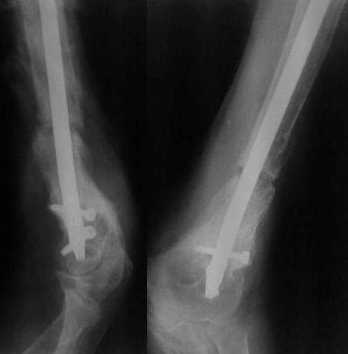

Более года назад пациент был оперирован в одном из НИИТО. При контрольном осмотре через год: болевой синдром, контрактура в локтевом суставе, патолгическая подвижность нижней трети плеча

|

Что этот пример должен подтвердить или опровергнуть?